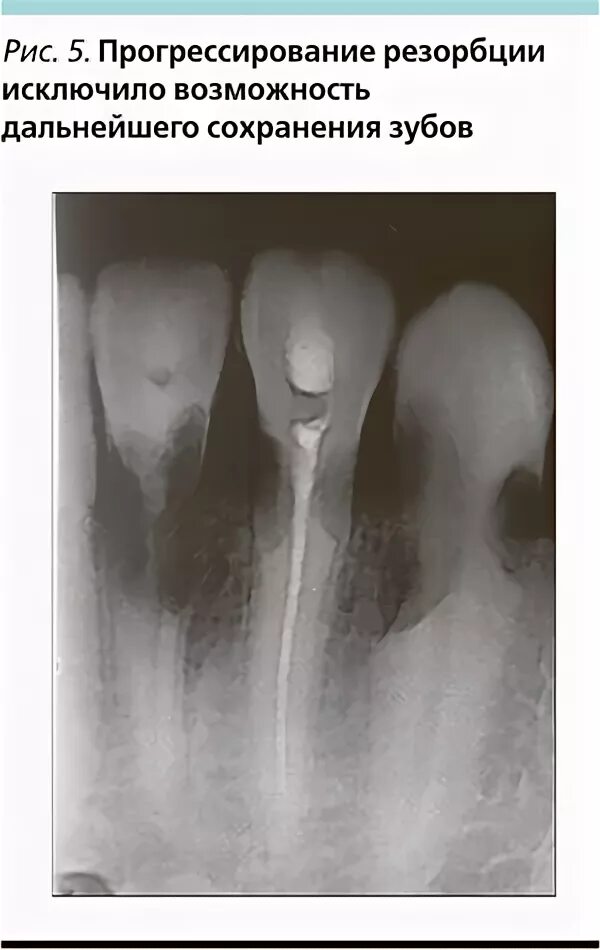

Резорбция епифанов